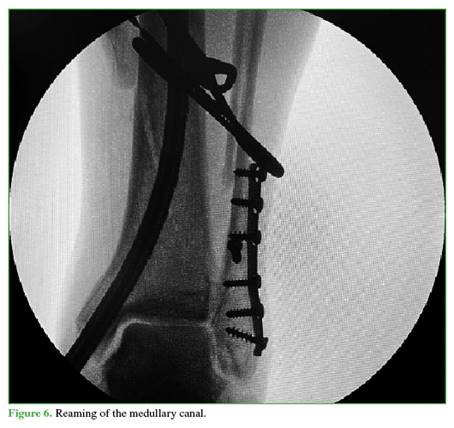

A 3 cm incision is then made distally from the tip of the tibial malleolus (Figure 2). Using a guidewire, the entry point is identified in the center of the tibial malleolus in both planes (Figures 3 and 4), and then enlarged with a cannulated reamer (Figure 5). An olive-tipped guidewire is inserted (Figure 6), and reaming of the medullary canal is performed through a soft tissue protector (Figure 7).

The nail of the preselected length is inserted under fluoroscopic guidance and anchored distally using the external targeting device, and proximally using a free-hand technique (Figures 8-10)